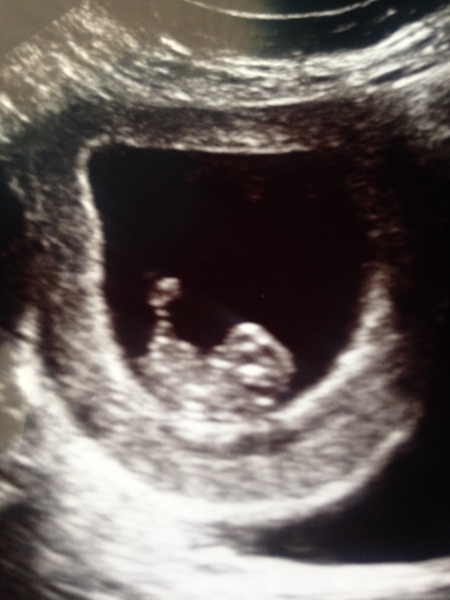

Lovely to see the early scan pics on here as well, so exciting. I have caved and booked one next week when I will be (fingers crossed) 8 weeks. Will it be abdominal or internal does anyone know?